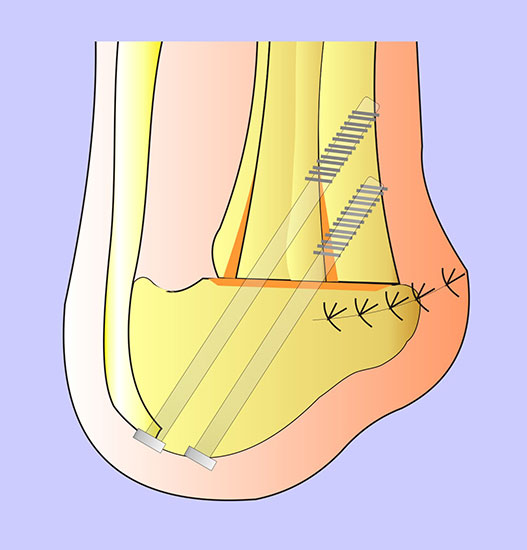

Zur Osteosynthese bevorzugen wir 2-3 kanülierte Großfragmentschrauben (Abb. 49). Postoperativ ist die Extremität für 8 Wochen zu entlasten, wobei zur Sicherheit eine Entlas­tungsorthese verordnet werden kann. Bei schwachen oder unzuverlässigen Patienten empfiehlt es sich, für 8 Wochen einen Ring-Fixateur anzulegen.